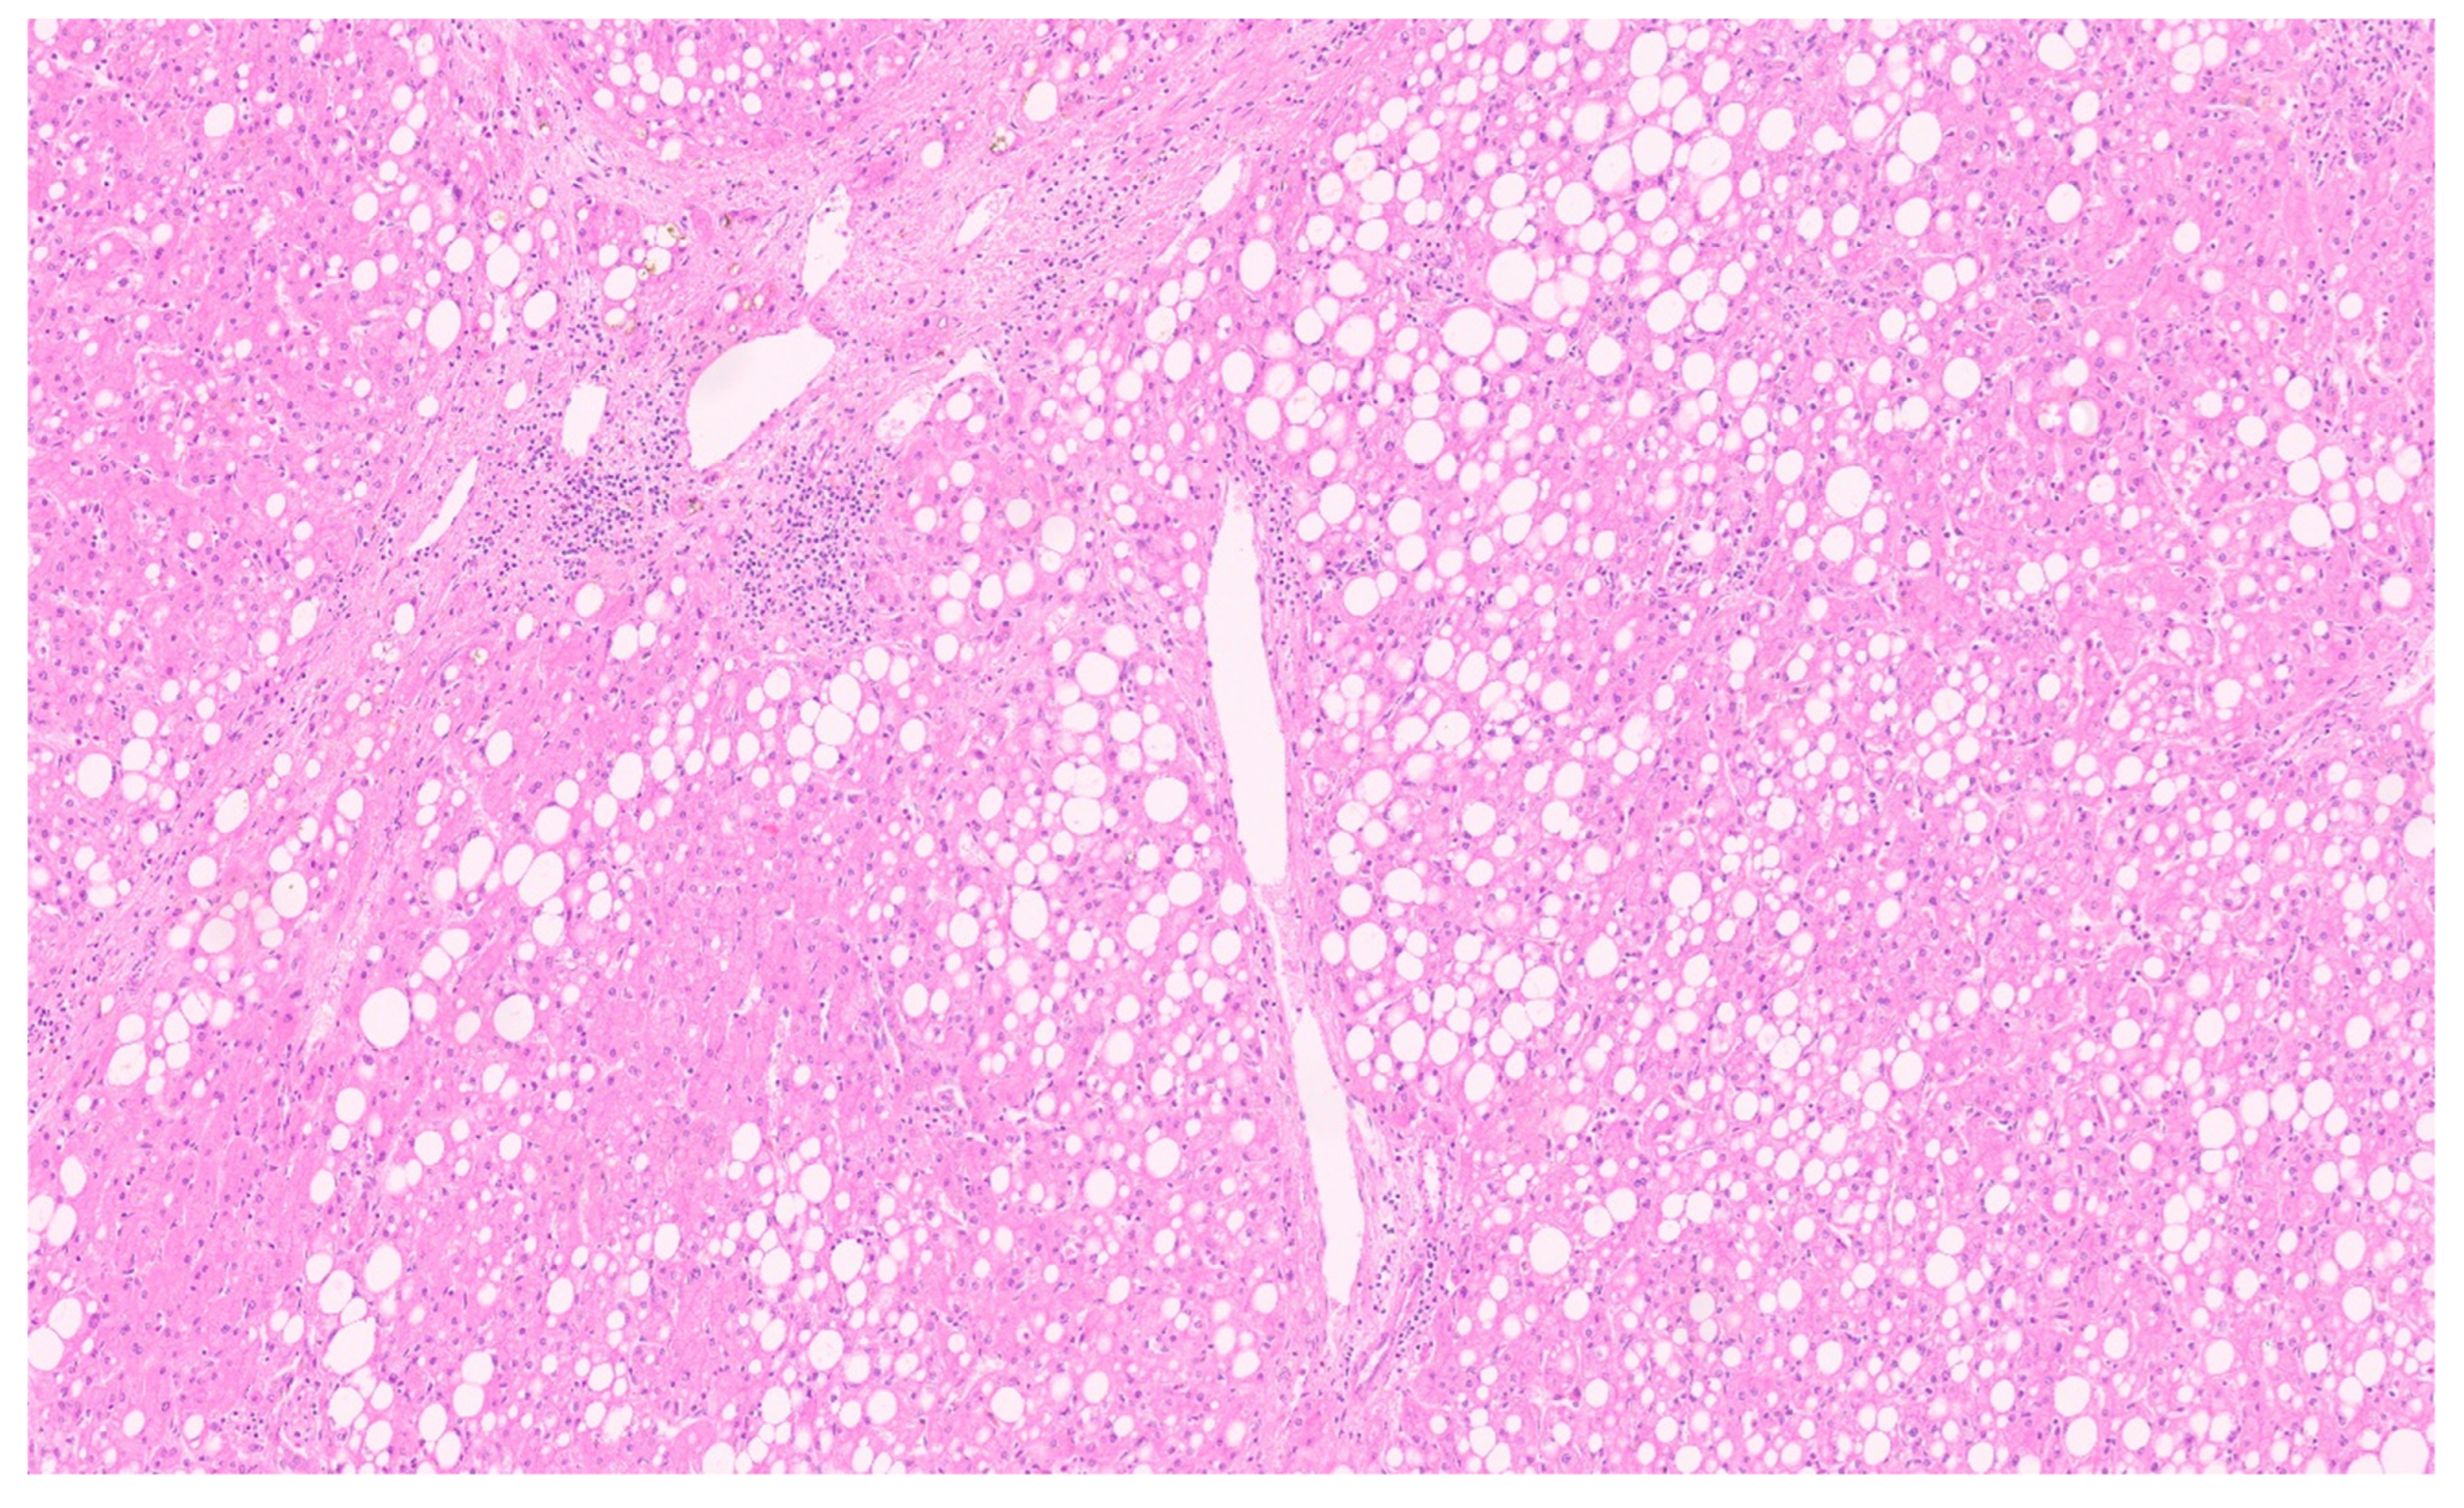

8. Pathology

- Martins-Filho, S.N.; Putra, J. Hepatic mesenchymal hamartoma and undifferentiated embryonal sarcoma of the liver: A pathologic review. Hepat. Oncol. 2020, 7, HEP19. [Google Scholar] [CrossRef]

- Stocker, J.T.; Ishak, K.G. Mesenchymal hamartoma of the liver: Report of 30 cases and review of the literature. Pediatr. Pathol. 1983, 1, 245–267. [Google Scholar] [CrossRef]

- Papke, D.J., Jr. Mesenchymal Neoplasms of the Liver. Surg. Pathol. Clin. 2023, 16, 609–634. [Google Scholar] [CrossRef]

- Rao, S.; Shetty, D.; Sharan, A.; Mukharji, S. Pediatric Mesenchymal Hamartoma of Liver: A Case Report with Histomorphological Differential Diagnosis and Review of Literature. Curr. Health Sci. J. 2022, 48, 230–234. [Google Scholar] [PubMed]